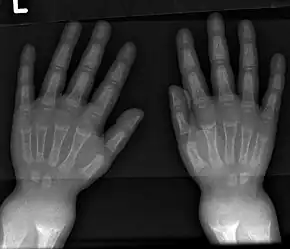

- Radiography typically show widening of the zones of provisional calcification of the metaphyses secondary to unmineralized osteoid. Cupping, fraying, and splaying of metaphyses typically appears with growth and continued weight bearing.[41] These changes are seen predominantly at sites of rapid growth, including the proximal humerus, distal radius, distal femur and both the proximal and the distal tibia. Therefore, a skeletal survey for rickets can be accomplished with anteroposterior radiographs of the knees, wrists, and ankles.[41]